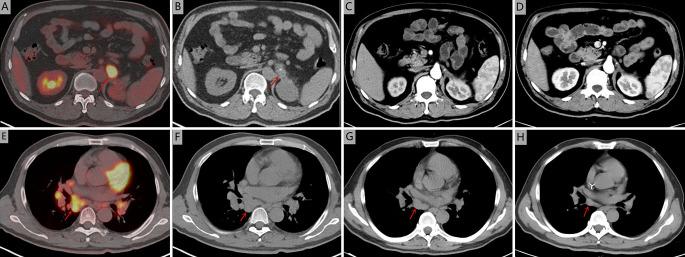

A 51-year-old man was admitted to Zhejiang Cancer Hospital, diagnosed with a recurrence of adrenal epithelioid angiosarcoma. He had undergone a surgical resection seven months earlier. Combination chemotherapy with liposomal doxorubicin and paclitaxel was administered. After two cycles of chemotherapy, his pain was relieved. Computed tomography (CT) suggested that the soft tissue tumour lesions in the surgical area had disappeared, mediastinal and mediastinal-hilar lymph nodes were significantly reduced or had disappeared, and the patient had achieved a partial response (PR). CT after six cycles of chemotherapy indicated that the patient had achieved a complete response (CR).

一名51岁男性入住浙江省肿瘤医院,被诊断为肾上腺上皮样血管肉瘤复发。他在七个月前接受了手术切除。给予脂质体阿霉素和紫杉醇联合化疗。化疗两个周期后,他的疼痛得到缓解。计算机断层扫描(CT)显示手术区域的软组织肿瘤病变消失,纵隔及纵隔-肺门淋巴结明显缩小或消失,患者达到部分缓解(PR)。化疗六个周期后的CT显示患者达到完全缓解(CR)。